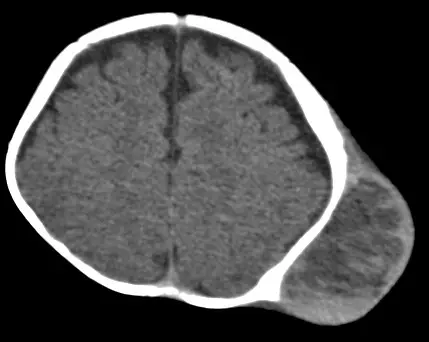

一位新生兒出生後有一巨大的頭皮血腫塊,臨床醫師安排電腦斷層以確定其病因,檢查發現該血腫塊侷限於左側頂骨 ( parietal bone )的範圍(如圖),而三個月後再追蹤的電腦斷層也見到吸收後的血腫塊出現鈣化,其最可能診斷是:

本電腦斷層影像為新生兒頭部橫切面,可見以下特徵:

- 頭皮外層巨大血腫:影像右側(對應解剖左側)可見一巨大頭皮凸起血腫,密度高於腦組織,位於顱骨外層

- 侷限性(suture-limited):血腫邊界清楚,侷限於單一顱骨(左側頂骨,parietal bone)範圍內,未跨越顱縫(cranial sutures),此為 cephalohematoma 最關鍵的診斷特徵

- 顱骨外層病灶:血腫位於骨膜下(subperiosteal),深於帽狀腱膜(galea aponeurotica)

- 顱內結構正常:腦實質無出血或受壓跡象,排除硬膜下血腫或腦內出血

- 後續追蹤:題目描述三個月後再次 CT 顯示血腫吸收後出現鈣化,符合 cephalohematoma 骨化/鈣化的自然病程